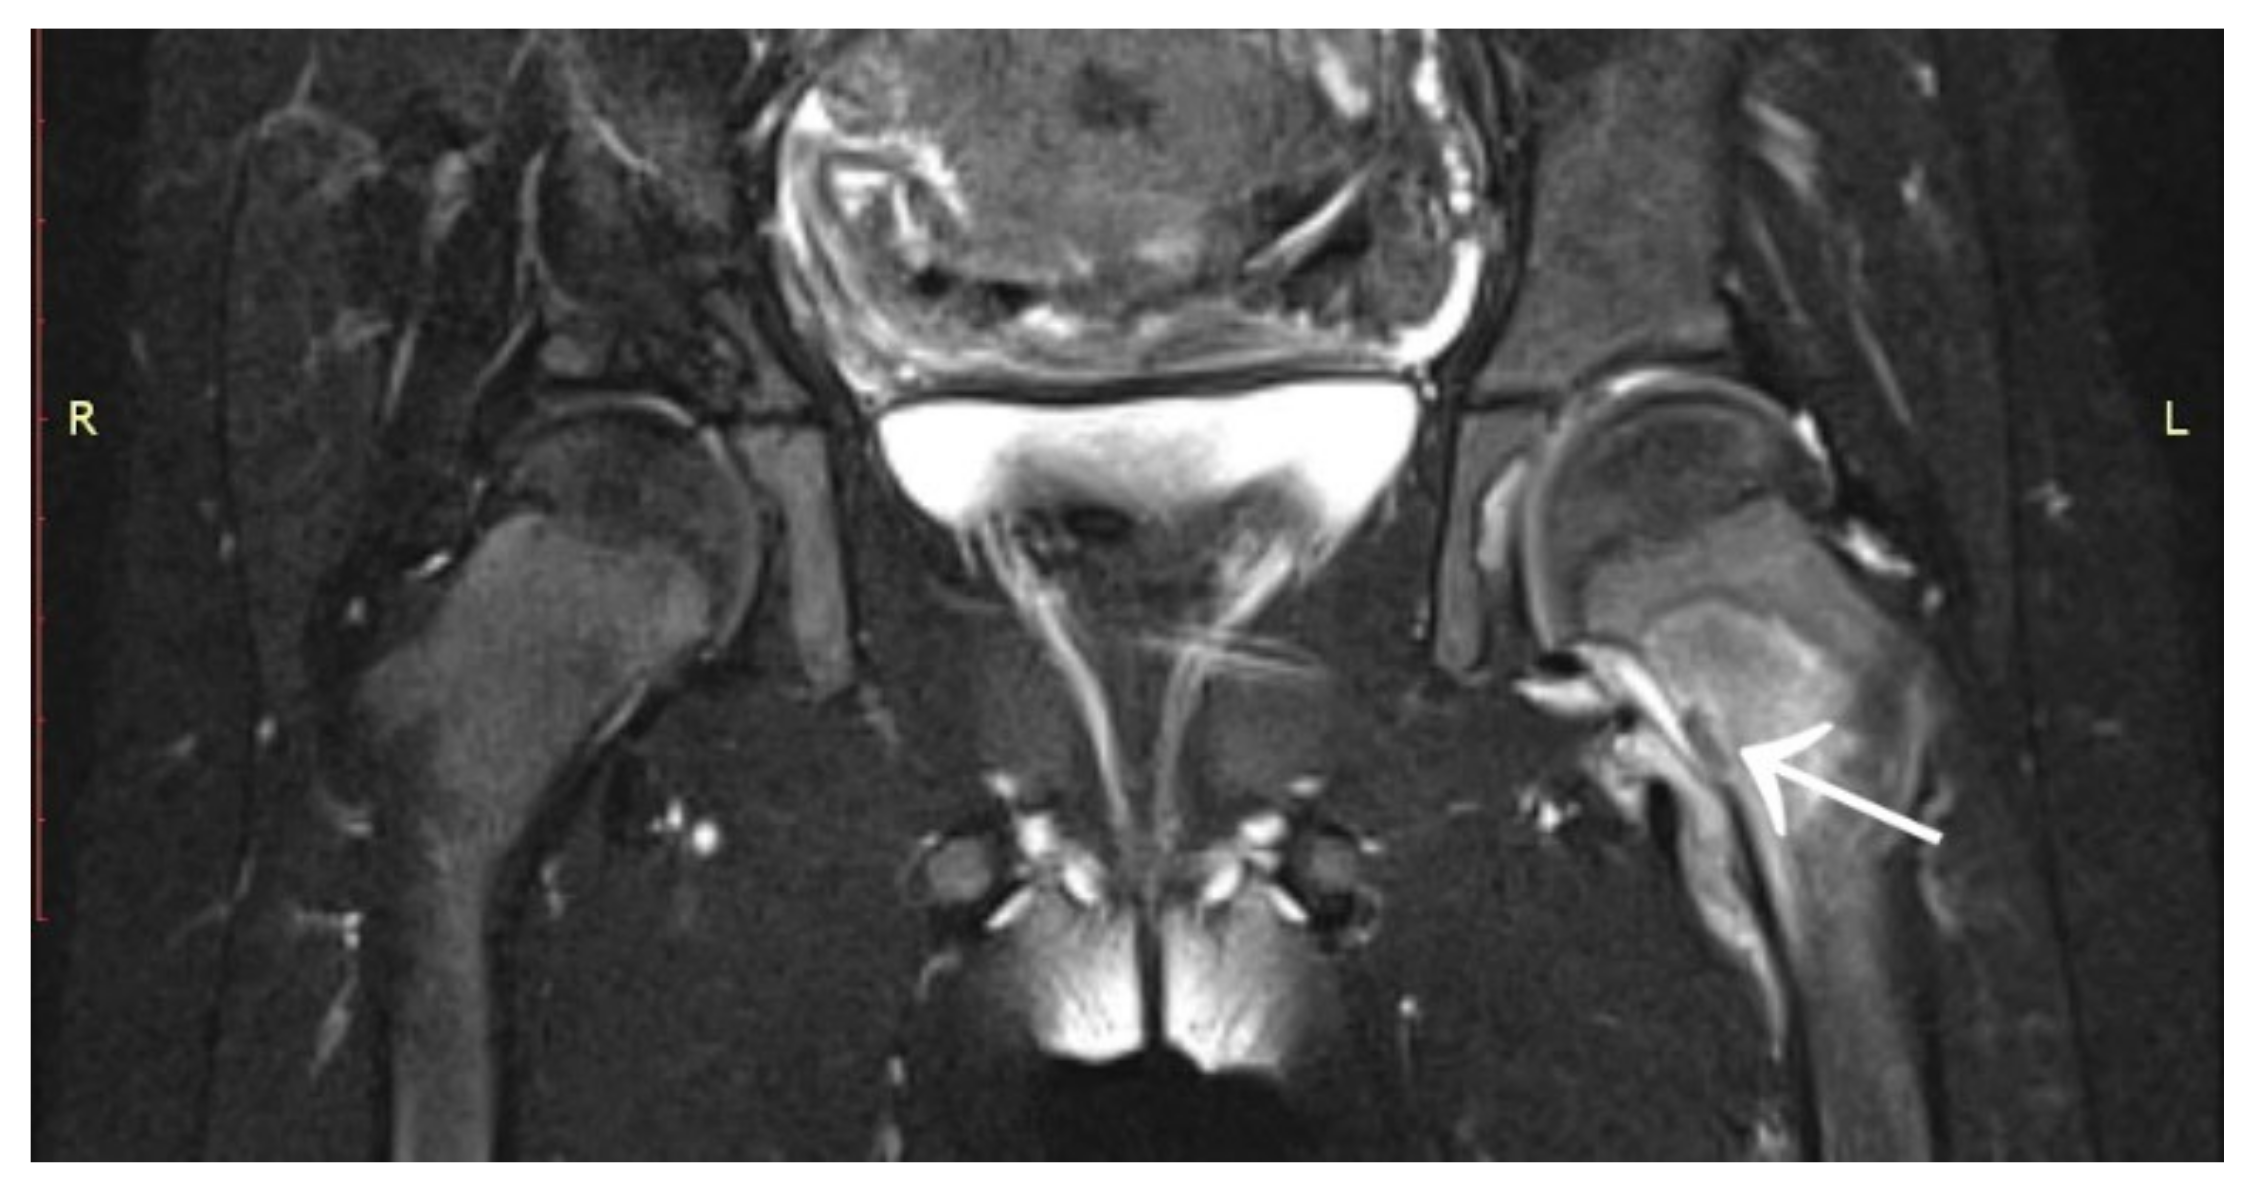

3.6. Case 6: OO Masking as Chronic Hip Arthritis

3.7. Case 7: OO Masking as a Meniscus Injury

3.8. Case 8: OO Masking as Juvenile Idiopathic Arthritis